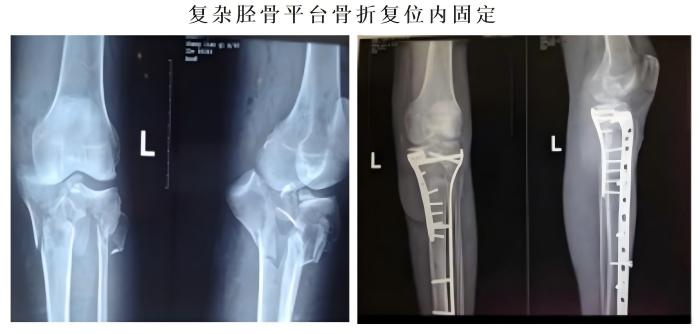

常规开展人体各部位骨折、脱位的修复重建。业务亮点:①我院骨科对于复杂胫骨平台的治疗方法获得国际“平台大师”罗从风教授的高度肯定,并将其编入胫骨平台骨折诊疗教程。②我院骨科通过Stoppa入路,结合传统入路的精髓,治疗复杂骨盆骨折,并在福建省率先使用骨折微创内支架治疗骨盆前环损伤。③对于四肢长管状骨骨折,我院骨科通过几个1-2CM的手术切口,闭合复位骨折,微创插钉,不破坏骨折端软组织及血运。不但减小了手术创伤,还提高了愈合速度。④我院骨科于国内首创使用“微创钛揽捆扎固定”,治疗肩锁关节脱位,完美解决传统手术手术创口大,肩关节活动差,内固定撞击等诸多缺点。